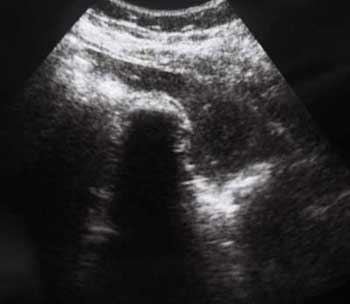

Инга

Похожий случай сегодня:

- IMG_6794a.jpg (11.82 КБ) 2712 просмотров

- IMG_6790a.jpg (8.79 КБ) 2712 просмотров